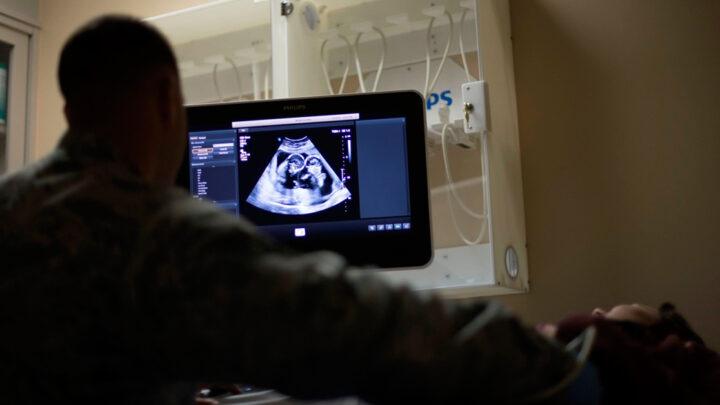

O que é ultrassonografia A ultrassonografia é também conhecida por ecografia e ultrassom, é um exame de diagnóstico que serve…